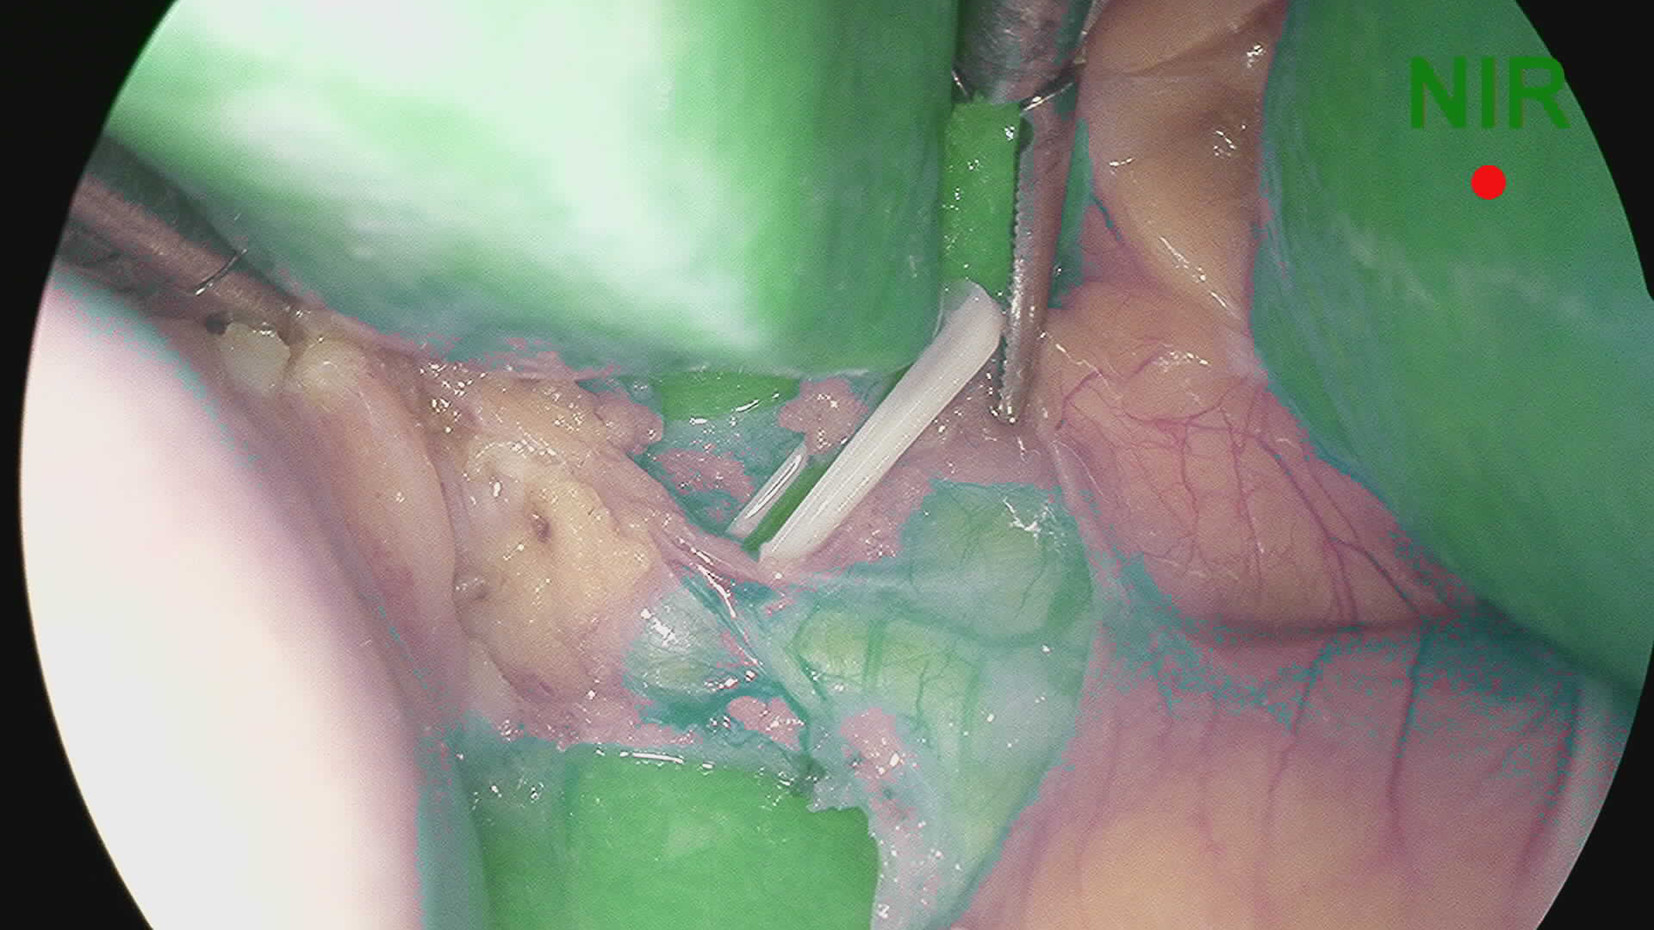

Application value of indocyanine green fluorescence imaging in laparoscopic cholecystectomy of difficult gallbladder

Abstract(1421) HTML (256) PDF (2744KB)(92)

Abstract:

Objective  To investigate the clinical utility of indocyanine green (ICG) fluorescence imaging in difficult laparoscopic cholecystectomy (LC).  Methods  The clinical data of LC patients from October 2021 to December 2021 in the First Affiliated Hospital of Anhui Medical University were retrospectively analyzed. Based on whether ICG fluorescence imaging was used and whether gallbladder difficulties were detected, the patients were divided into four groups: ICG common gallbladder (Group A), ICG difficult gallbladder (Group B), common gallbladder (Group C), and difficult gallbladder (Group D). The operative time, intraoperative bleeding, length of hospital stay, hospitalization cost and postoperative complications were compared. Comparison of normally distributed continuous data between groups was performed by t test. Comparison of categorical data between groups was performed using the chi-square test or Fisher's exact probability method.  Results  The operative time, intraoperative bleeding, length of hospital stay, hospitalization cost and intraoperative complications in group A were comparable to those in Group C (all P > 0.05). The operative time and intraoperative bleeding were (75.41±12.96) min and (18.27±6.97) mL in group B, vs (106.78±19.21) min and (23.99±8.43) mL in group D, respectively, and the differences were statistically significant (all P < 0.05), while the length of hospitalization, hospitalization cost and postoperative complications in group B were comparable to those in group D (all P > 0.05).  Conclusion  The benefits of ICG fluorescence imaging during LC in patients with the common gallbladder are not obvious. However, in difficult gallbladder cases, ICG fluorescence imaging can improve biliary tract exposure and reduce operation time and intraoperative bleeding.